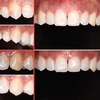

Zirconium Applications

Porcelain Applications

Laminate Veneer